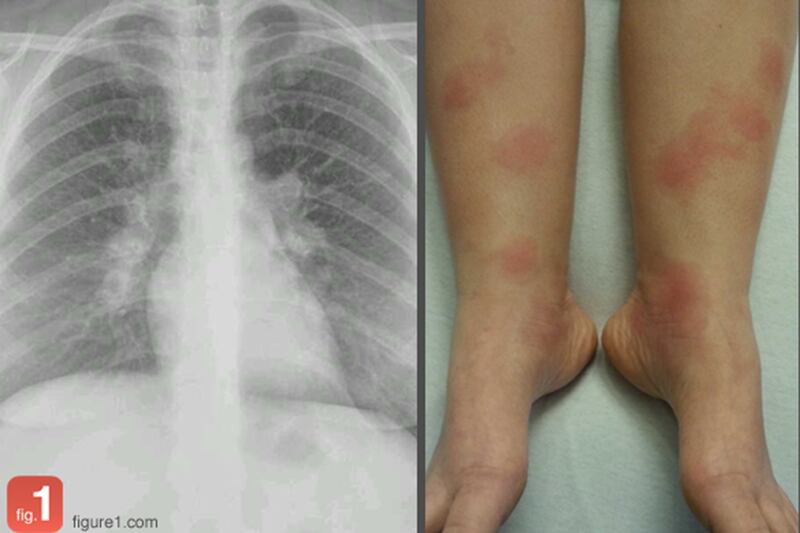

Meet Figure-1, which is being fairly accurately touted in the media as “Instagram for Doctors,” a new photo-sharing service for iPhone and Android that allows health care professionals to upload images from their cases for educational and professional purposes. Since laypeople can also download the app, which features endless scrolling through wounds, pustules, tumors, and X-rays, it could just as easily be billed as “Instagram for Doctors, Serial Killers, And People Who Think They Have It Bad But Want To Be Proven Otherwise.”

That said, it provides those in the health biz an invaluable, and ingenious, tool for teaching, treating, and diagnosing tricky symptoms. One scroll through the comments section of a post—full of questions, suggestions, and answers—will prove positive this is a working concept.

What are you missing? What gory details are in there? Here are five samples to whet your appetite (for destruction).

A word of warning: These are the tamest, most SFW images we came across, but if you want to dig in and see the real deal in all of its gnarly, open wound, puss-gushing, bone fragmented glory, get yourself to the app store of your choice and download away. Bonus: It’s free.